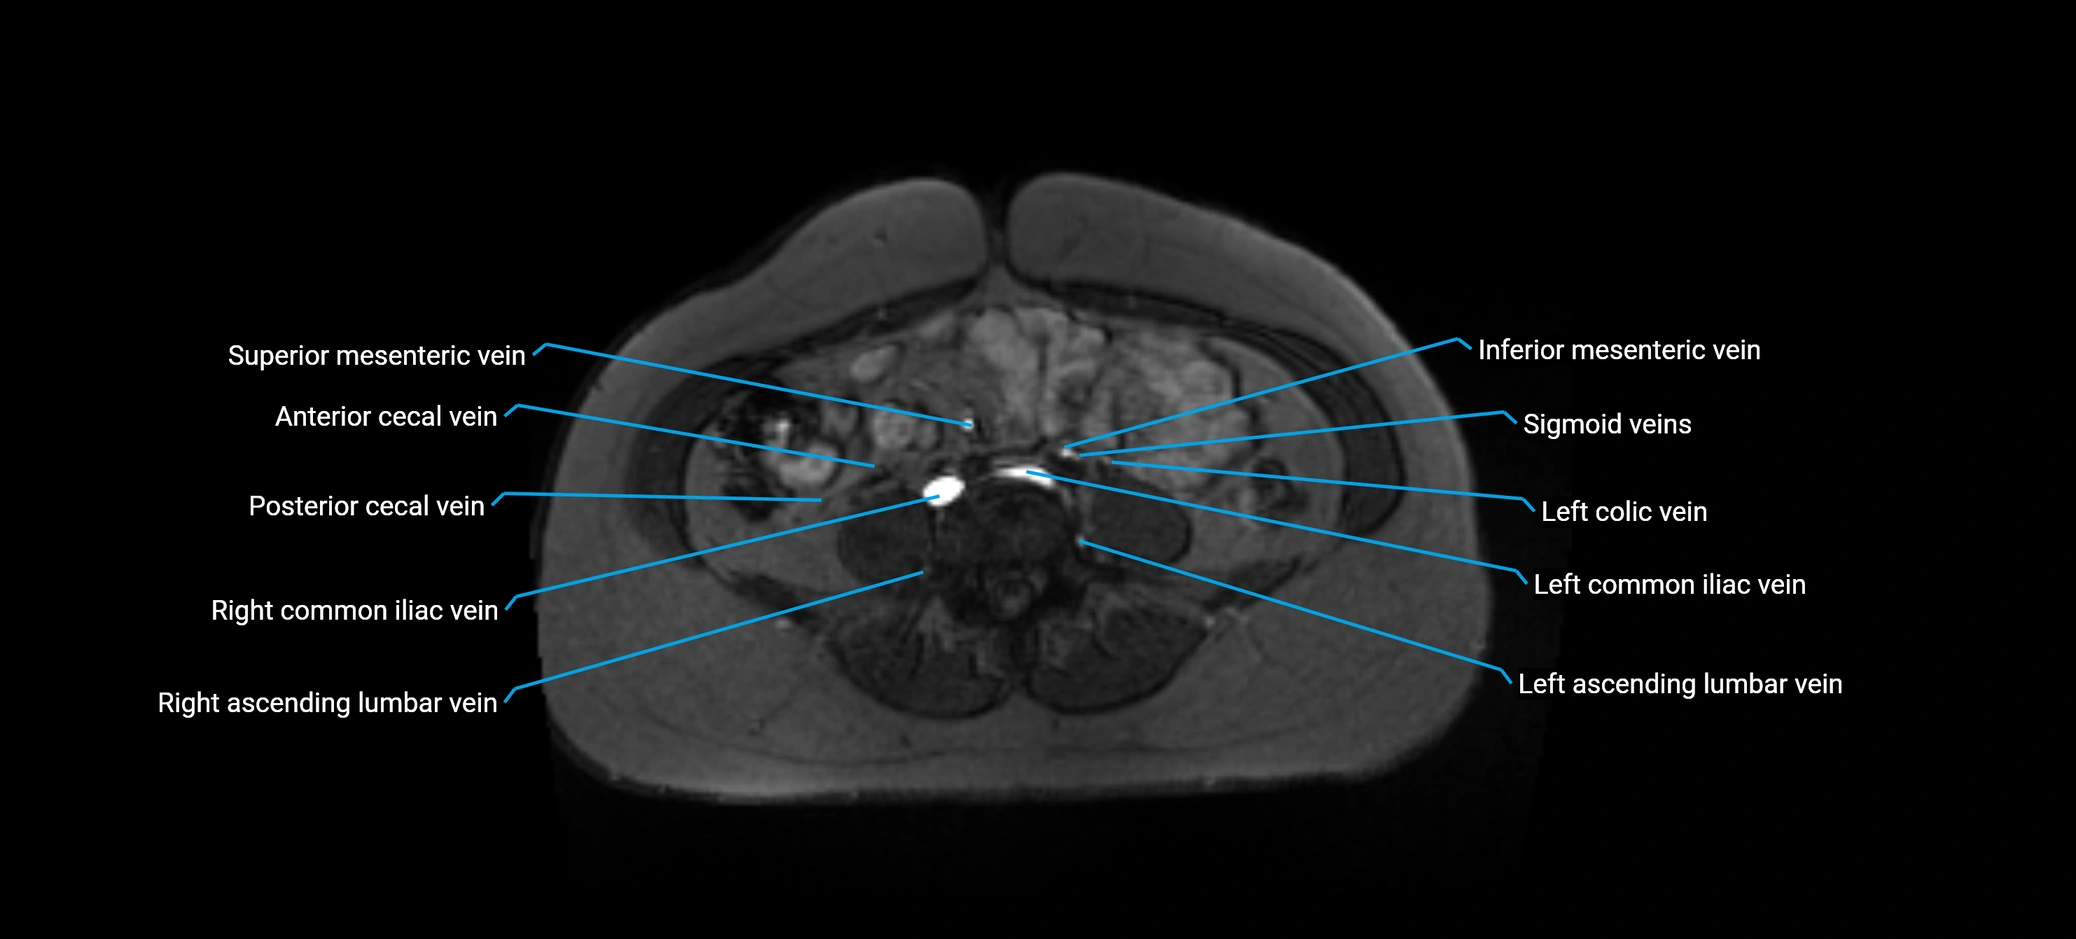

MRI image

image